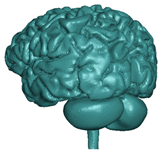

| White matter—left/right hemisphere | THUMS MAT_VISCOELASTIC 2 [35] | 1.00 × 10−9 | Bulk modulus 2.16 × 10−3 | G0 = 12.5 × 10−3 G1 = 6.125 × 10−3 | hexa 231,146/ 237,494 |   |

| Grey matter—left/right hemisphere | THUMS MAT_VISCOELASTIC 2 [35] | 1.00 × 10−9 | Bulk modulus 2.16 × 10−3 | G0 = 10 × 10−3 G1 = 5 × 10−3 | hexa 313,176/ 311,954 |   |

| Cerebellum brainstem | F.A.O. Fernandes et al., 2018 [30] | 1.04 × 10−9 | – | Ν = 0.49999 Mu1 = 0.0012 Alpha1 = 5.05007 | hexa 204,567 |  |

| Corpus callosum | THUMS MAT_VISCOELASTIC 2 [35] | 1.04 × 10−9 | same as for WM | same as for WM | hexa 3190 |  |